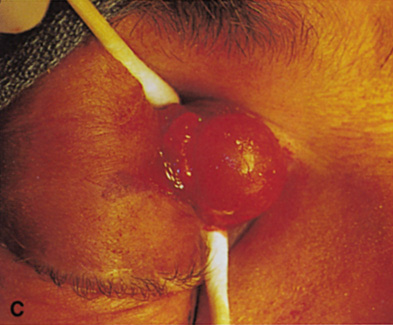

Fig. 6. Lateral orbitotomy through upper eyelid skin crease A. Photo demonstrating right globe ptosis present for more than 2 years. B. Axial CT scan showing a well outlined oval lesion in the lacrimal gland

fossa. C. Coronal CT showing lesion pushing globe inferiorly. D. Skin crease excision marked for lateral orbitotomy. E. Lateral orbital rim exposed. Bone cuts made above frontozygomatic suture

and at zygomatic arch. F. Lateral wall removed. Subperiosteal space exposed. Hard tumor could be

palpated in area of lacrimal gland. G. Benign mixed tumor of lacrimal gland removed. H. Bone sutured into place. I. Skin crease closed. |